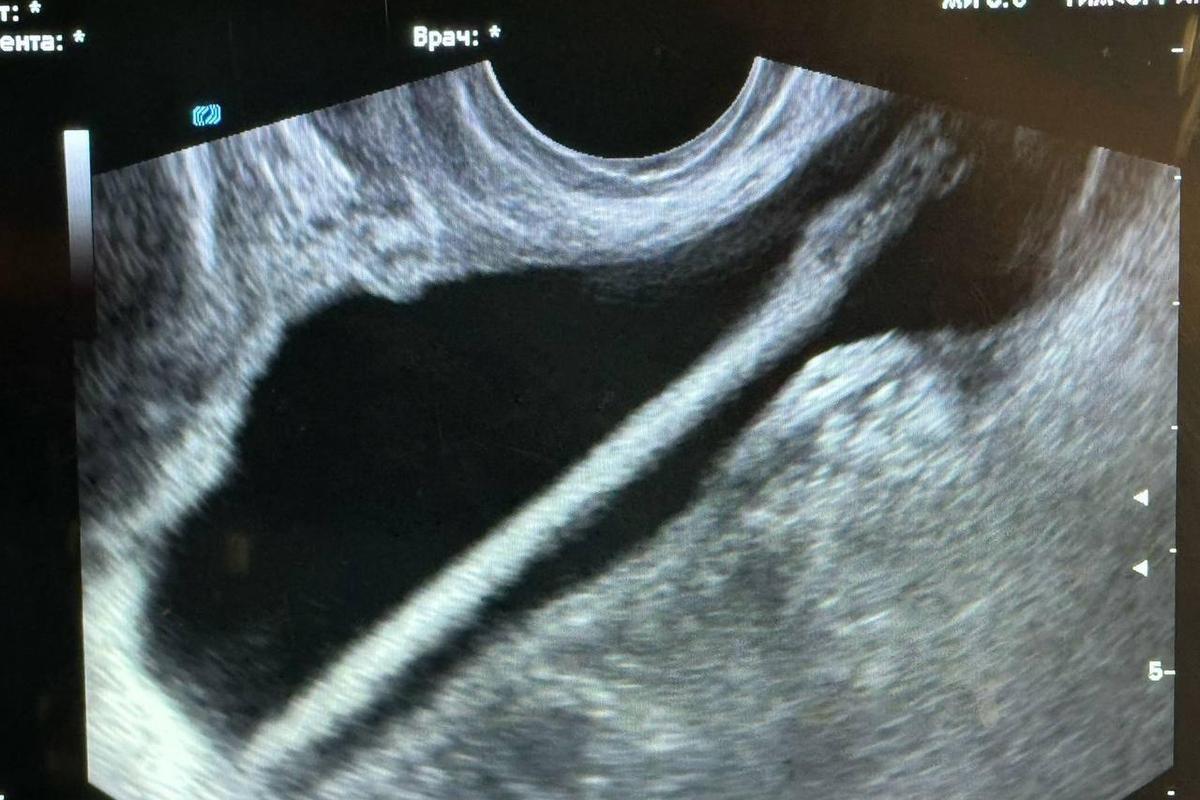

Заведующий отделением Петр Сысоев пояснил, что первоначально было проведено ультразвуковое исследование. Затем доктора осуществили хирургическую операцию, в ходе которой при помощи эндоскопа удалось извлечь инородный объект из мочевыделительной системы. Он добавил, что процедура прошла успешно и без осложнений.